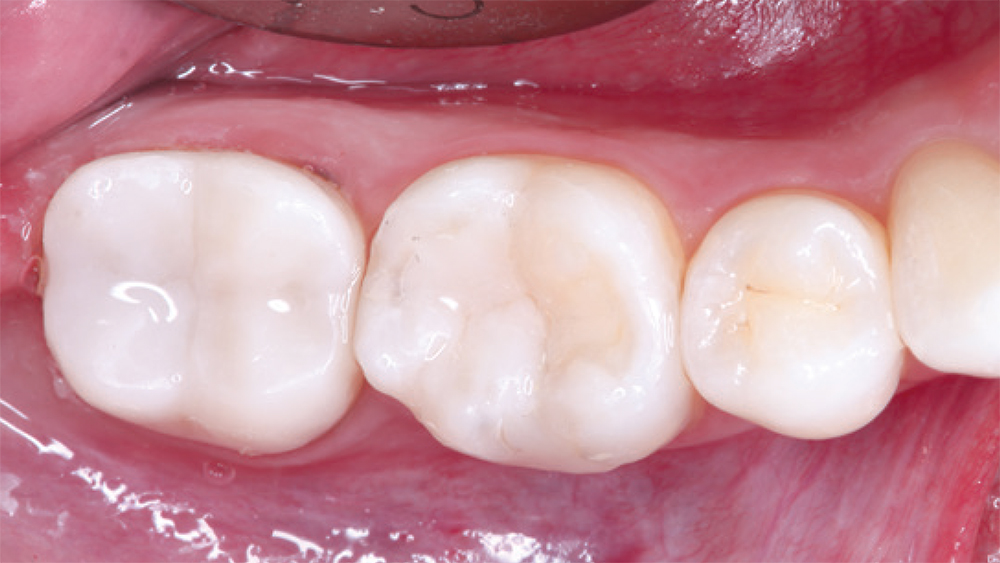

teeth #2

teeth #3

patient's fillings on teeth #2 and #3

In this case, the patient’s fillings on teeth #2 and #3 were removed and the teeth were prepared. During the same appointment, the doctor scanned the patient’s teeth and fabricated onlays from CAMouflage NOW milling blocks using the glidewell.io In-Office Solution. The onlays were delivered following a scientifically validated bonding protocol, maximizing the longevity of the nanohybrid composite restorations.